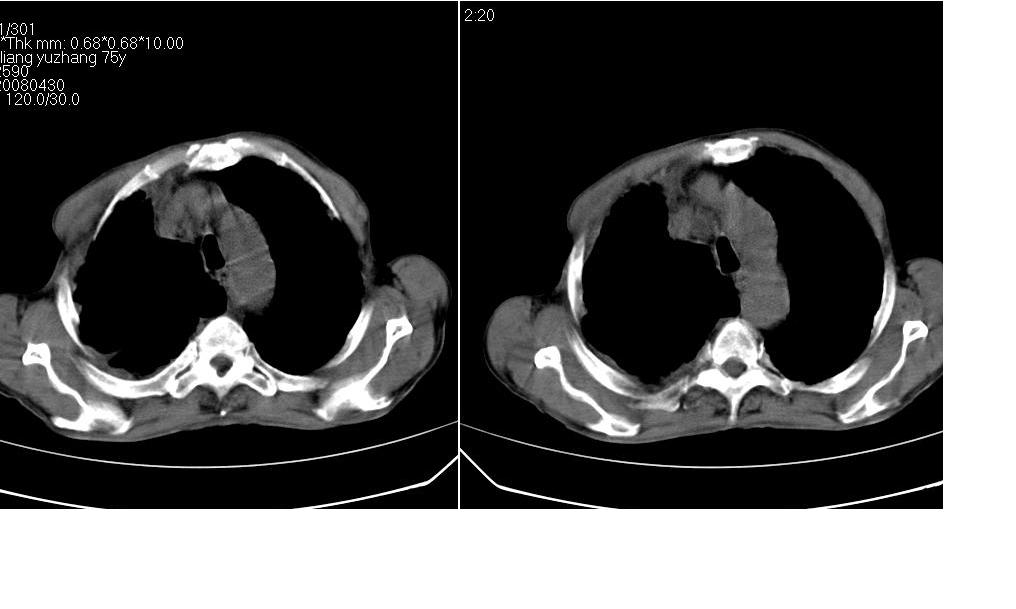

以下是引用zsl6918在2008-5-3 19:53:00的发言:[br]右肺中心型肺癌并纵隔淋巴结转移,胸膜转移,右肺癌性淋巴管炎。

以下是引用liuyue在2008-5-3 20:49:00的发言:[br]1.右侧中心型肺癌伴双肺转移瘤、纵隔淋巴结转移、右侧胸腔积液(侵及胸膜所致可能性大)。[br]2.右肺阻塞性肺炎,癌性淋巴管炎不除外。